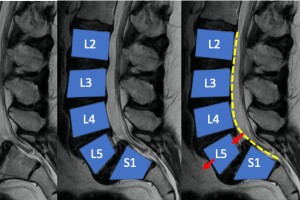

椎体滑脱

一椎体向前滑移至另一椎体上,通常导致腰部疼痛和僵硬。